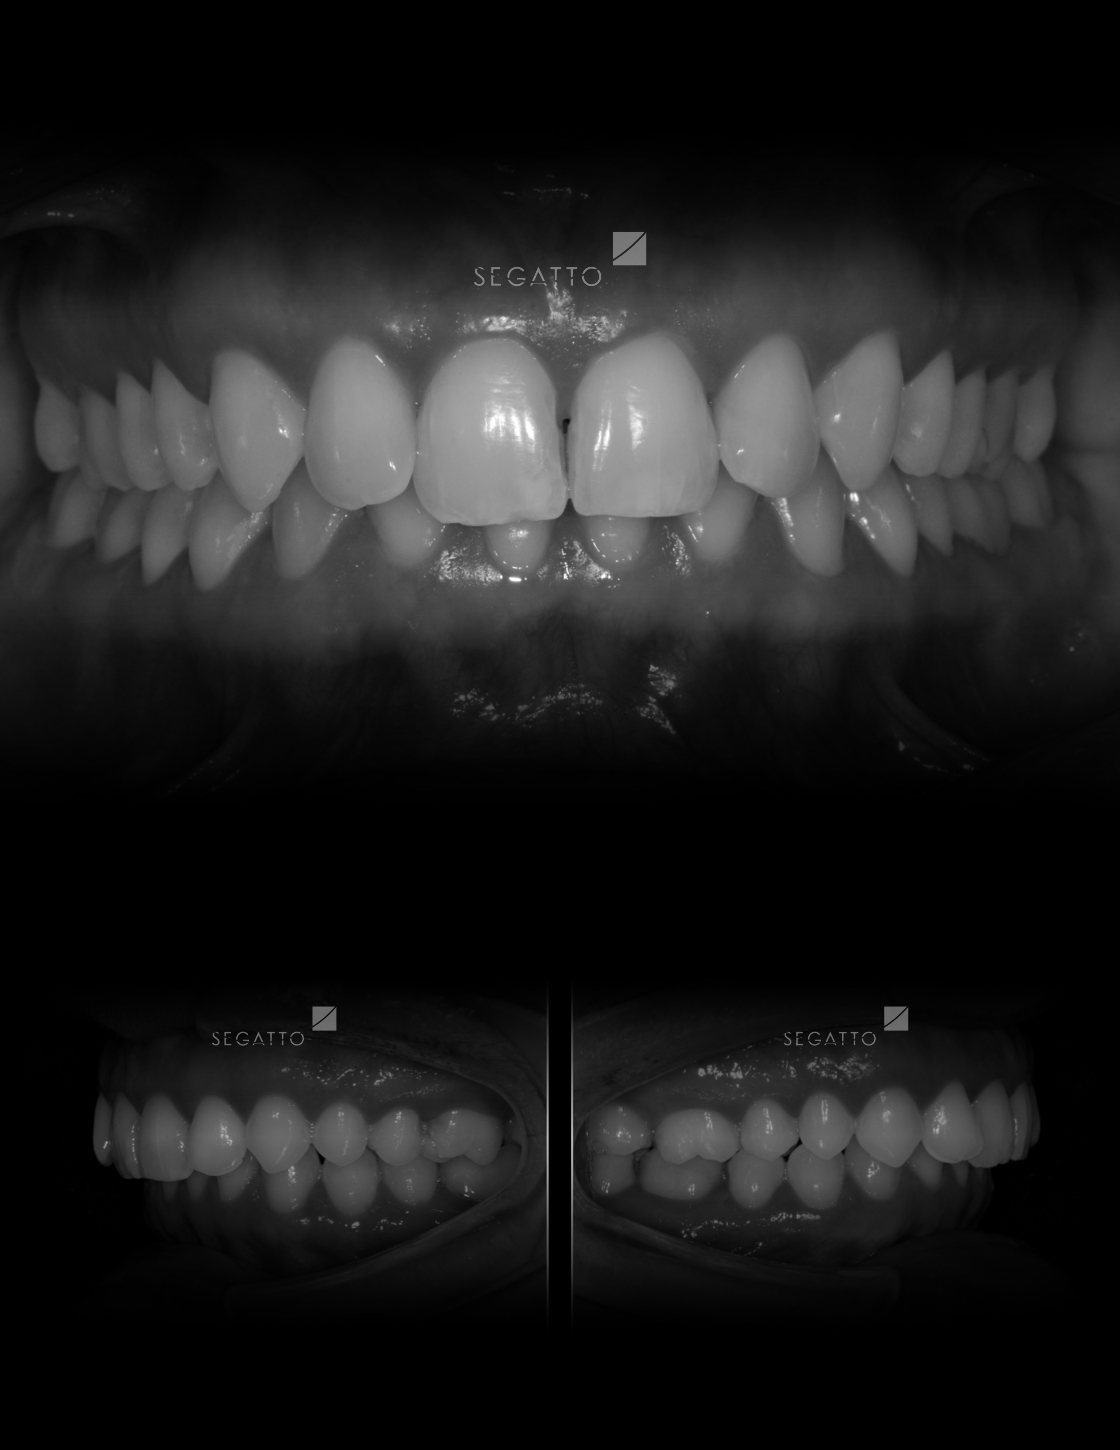

Orthodontics

Cases